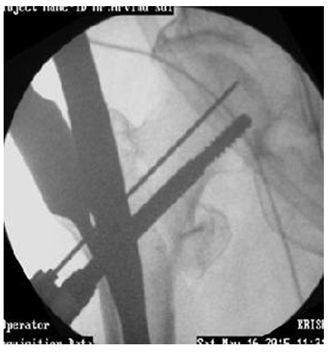

Hip pin and compression screw

Hip pin to be shorter than compression screw. Deep positioning to maintain tip apex distance. Head screws to be tightened alternately for compression. But may sink inside bone (Figure 31,32).

Figure 31 Hip pin to be shorter than compression screw. Deep positioning to maintain tip apex distance.

Figure 32 Head screws to be tightened alternately for compression. But may sink inside bone.

Reaming if Guide wire bends

1. Hand reamer.

2. Reverse reaming forward.

3. Gentle to and fro.

4. Gentle forward and backward.

5. Mostly bend straightens out. But careful. May break hence remove early (Figure 31 & 32).